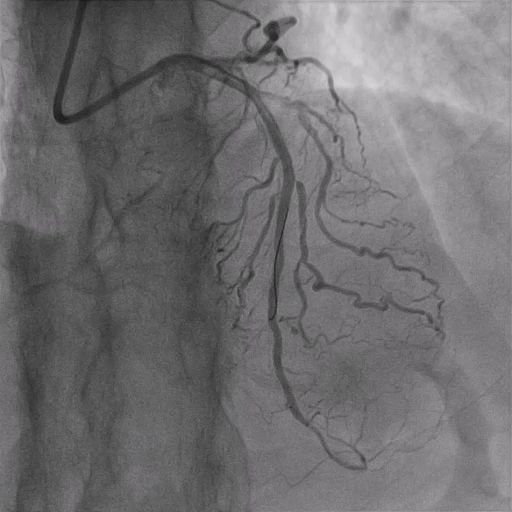

Bilateral 6Fr femoral access was obtained for staged PCI to the RCA CTO. The antegrade approach using a Gaia Next 2 wire entered the mid-RCA, but ADR with a Recross microcatheter and CP12 wire failed. A retrograde approach via the PL branch was then attempted using a SUOH3 wire, with reverse CART performed using a 2.5-mm balloon and CP12 wire. The Caravel microcatheter could not cross the CTO due to lesion rigidity, and the antegrade system was lost. The retrograde system was re-established with a Turnpike 150 microcatheter, which successfully traversed the lesion and was externalized using an RG3 wire snared into the antegrade JR4 guide. During retrograde microcatheter withdrawal, the patient developed severe chest pain and hypotension (due to stretching of LV i.e., billowing), requiring stabilization with intravenous adrenaline and dopamine. After the antegrade microcatheter crossed the lesion, the retrograde system was withdrawn. The RCA was predilated with 2.0- and 2.5-mm balloons, then stented with overlapping 3.0/44-mm and 3.5/44-mm stents, followed by postdilation with NC 3.5- and 4.0-mm balloons. During the final IVUS run, the IVUS catheter became trapped at the proximal RCA stent; it was retrieved by cutting the catheter, inserting a V18 wire into its lumen, and withdrawing it through a 6Fr guide extension. Final angiography demonstrated well-expanded stents with TIMI 3 flow in the RCA.

Case Summary